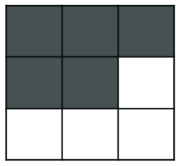

where is the mask of an ellipse parametrized by . As minimizing such a term is not straightforward, the authors optimize the energy functional iteratively, i.e. by finding the best for a fixed and then optimizing for a fixed . For complex shapes that are hard to parametrize, an alternative approach is to fit a shape template to the current segmentation as proposed in (Freedman and Zhang, 2005). Veksler (2008) proposed to incorporate a more general class of shapes, known as star shapes, into graph-based segmentation. In Veksler’s work, it is assumed that the center point () of the object is given. According to their definition, “an object has a star shape if for any point inside the object, all points on the straight line between the center and also lie inside the object” (Figure 13). The following pairwise term was introduced to impose the star shape prior:

| (33) |

This prior is particularly useful for segmentation of convex objects, e.g. optic cum and disc segmentation (Bai et al., 2014).